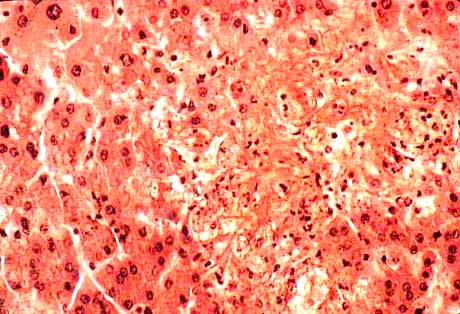

10-1-4.jpg (30891 bytes)

Fig.10-1-4: Giant-cell arteritis.

This lesion is focal and may be missed in a biopsy. Also the giant cells have focal distribution. It may consist of only initial thickening of the intima with or without lymphocytic reaction, with or without giant cells. There is fragmentation of the internal elastic membrane. The giant cells are Langhans type with peripherally placed nuclei. The initial damage is probably to the smooth musculature of the media with secondary damage of the internal elastic membrane which becomes fragmente

6-Arteritis: polyarteritis nodosa. necrotizing angitis, Giant-cell arteritis

Hepatic arteries are involved in two thirds of the patients affected by polyarteritis nodosa. There is an increased incidence of polyarteritis nodosa in chronic hepatitis B. Intra-parenchymal arteritides, especially in the portal fields, is usually overlooked because of the rarity of their occurrence and because they are confused with non-specific portal inflammations. Also intra parenchymal veins may be affected by vasculitis. Necrotizing angitis is commonly seen in drug addicts. Giant cell arthritis affects most frequently the cranial vessels but the condition is generalized and it can involve the aorta. The arteries of the liver are very rarely involved.